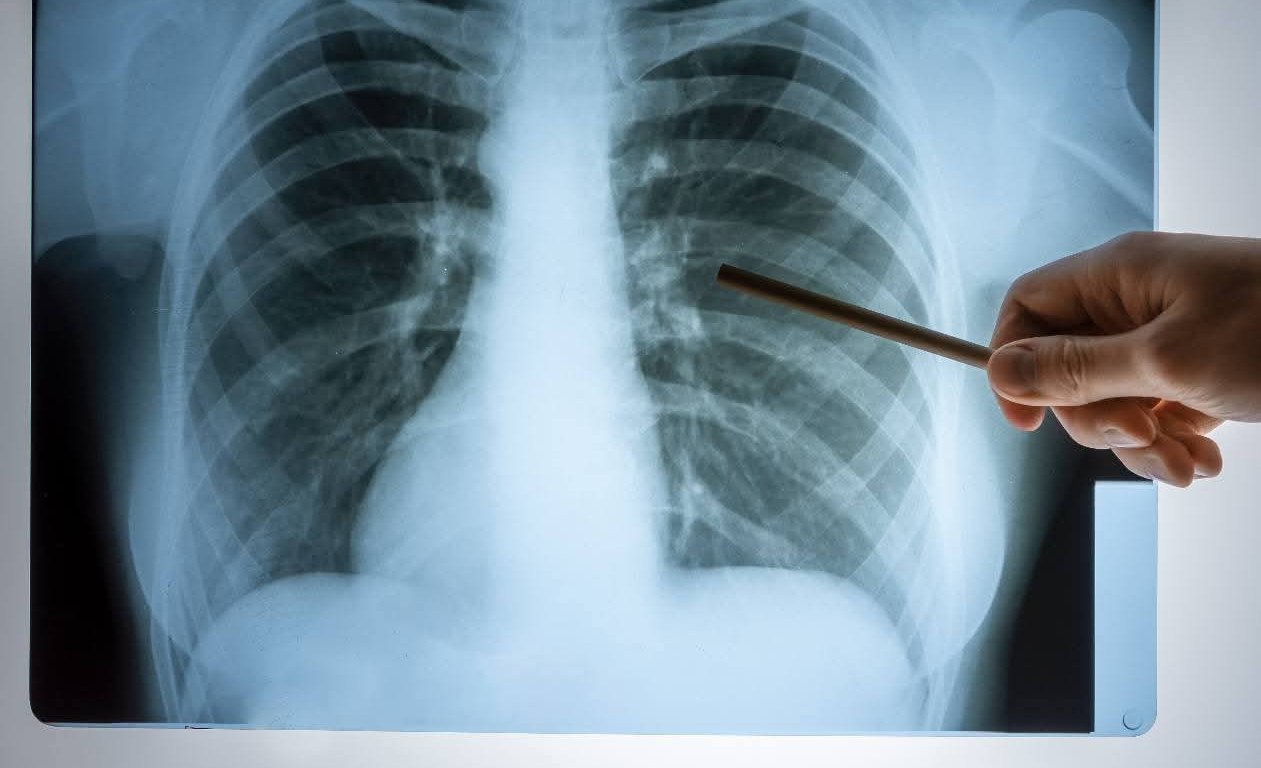

จากข้อมูลล่าสุดของสถาบันมะเร็งแห่งชาติ พบว่า มะเร็งปอด กำลังเป็นภัยเงียบคร่าชีวิตคนไทยสูงถึง วันละ 40 ราย และมีผู้ป่วยรายใหม่เพิ่มขึ้นเฉลี่ย วันละ 48 ราย สะท้อนความรุนแรงของโรคที่มาพร้อมกับวิกฤตมลพิษทางอากาศ โดยเฉพาะ ฝุ่น PM2.5 ซึ่งองค์การอนามัยโลก (WHO) ยกให้เป็นสารก่อมะเร็งกลุ่มหนึ่ง เช่นเดียวกับบุหรี่

ในงาน “มะเร็งรู้ทัน ป้องกันเป็น รักษาได้”จัดโดยชมรมฟื้นฟูสุขภาพผู้ป่วยโรคมะเร็ง รศ.นพ.นรินทร์ วรวุฒิ ให้ข้อมูลกล่าวว่า องค์กรอนามัยโลก (WHO) คาดการณ์ว่า จำนวนผู้ป่วยมะเร็งทั่วโลกจะเพิ่มขึ้นมากกว่าร้อยละ 77 ภายใน 25 ปีข้างหน้า สำหรับสถิติมะเร็งในประเทศไทย ในปี 2022 ข้อมูลจากสถาบันมะเร็งแห่งชาติพบว่าแต่ละปีมีคนไทยป่วยด้วยโรคมะเร็งรายใหม่ ประมาณ 140,000 คน เสียชีวิตประมาณ 83,000 คน เฉลี่ยวันละ 227 ราย มะเร็งเต้านมยังคงมีสถิติเป็นอันดับหนึ่ง มะเร็งปอดตามมาเป็นอันดับ 2 แต่มีสถิติที่น่าตกใจ พบผู้ป่วยมะเร็งปอดรายใหม่เฉลี่ยวันละ 48 คน และมะเร็งปอดคร่าชีวิตคนไทยวันละ 40 ราย

สิ่งที่น่ากลัวมากในปัจจุบัน คือ อากาศเป็นพิษเต็มไปด้วย PM 2.5 เมื่อสูดดมเข้าสามารถเข้าไปลึกถึงหลอดลมจนกระทั่งเข้าไปในกระแสเลือดได้ ทำให้เกิดผลต่างๆ ต่อร่างกาย โดยเฉพาะในระบบทางเดินหายใจนั้น ทำให้ถุงลมโป่งพอง มีพังผืด มีแผลในปอด ปอดอักเสบ ติดเชื้อง่าย ส่งผลให้เป็นมะเร็งปอดได้ เพราะ PM 2.5 สามารถกระตุ้นให้เซลล์กลายพันธุ์อยู่แล้วแต่ยังไม่เป็นมะเร็งกลายพันธุ์เป็นเซลล์ต้นกำเนิดมะเร็งได้